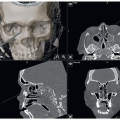

Cone-beam computed tomography (CBCT) or spiral CT scan

Preoperative CBCT or spiral CT with lateral and posteroanterior cephalogram